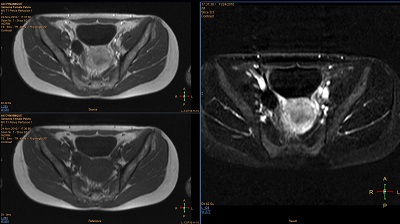

Subtraction

Perform basic calculations between two volumes

Enables basic calculations between two volumes, including addition, subtraction and ratio from within a single dynamic series.

• The application allows to subtract pre-contrast from post-contrast series.